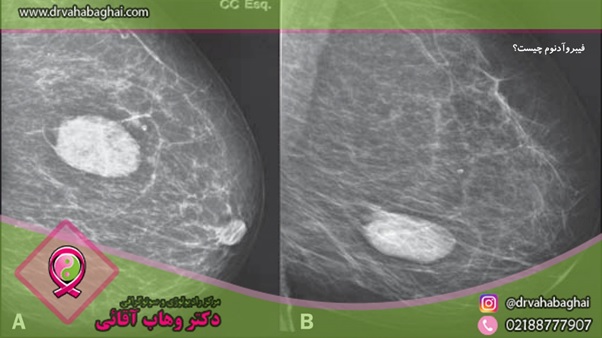

•       ماموگرافی: در ماموگرافی از اشعه ایکس برای ایجاد تصویری از بافت پستان استفاده می شود. این تصویر ماموگرام نام دارد و می تواند مرزهای فیبروآدنوم را تشخیص دهد و آن را از سایر بافت ها متمایز کند. بافت متراکم سینه، تشخیص تفاوت بین بافت معمولی پستان و آنچه ممکن است فیبروآدنوم باشد را دشوارتر می کند. همچنین، به دلیل خطر تشعشعات ناشی از ماموگرافی، معمولاً برای بررسی توده های سینه در افراد زیر 30 سال استفاده نمی شود.